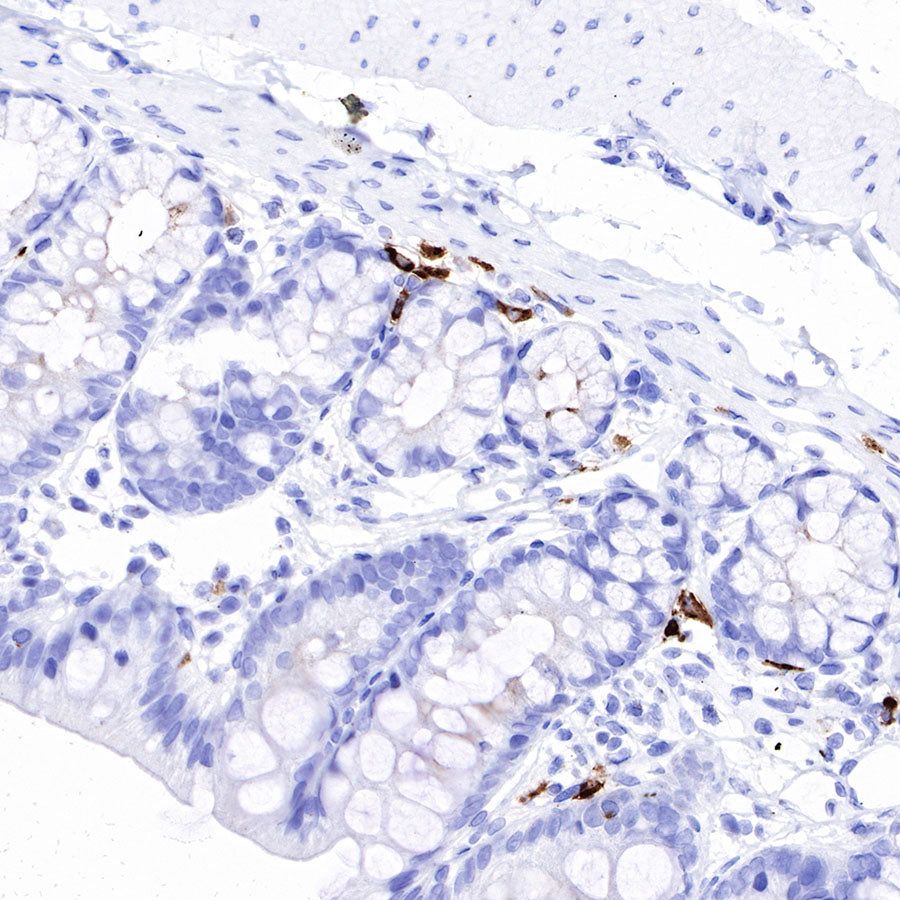

Immunohistochemistry

IHC shows positive staining in paraffin-embedded rat colon. Anti-IGJ antibody was used at 1/1600 dilution, followed by a HRP Polymer for Mouse & Rabbit IgG (ready to use). Counterstained with hematoxylin. Heat mediated antigen retrieval with Tris/EDTA buffer pH9.0 was performed before commencing with IHC staining protocol.